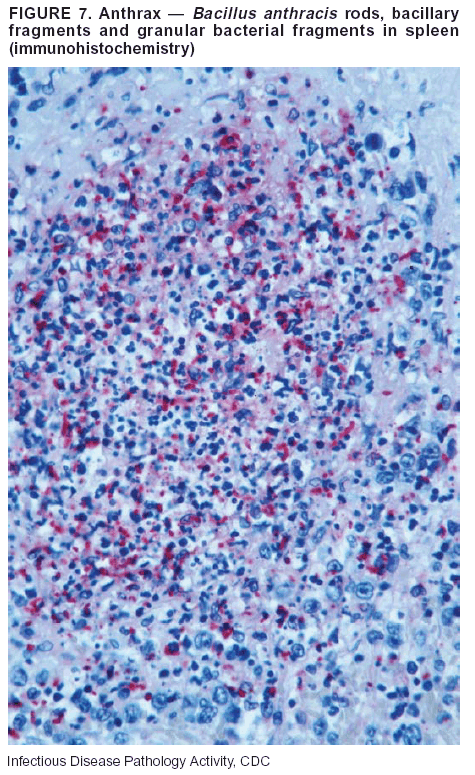

Pathologic Findings. Anthrax has three pathologic forms. Cutaneous anthrax is characterized by an eschar that forms where the bacteria entered the skin (Figure 2). Microscopically, the epidermis has necrosis and crusts, whereas the dermis demonstrates necrosis, edema, hemorrhage, perivascular inflammation, and vasculitis. The lymph nodes that drain the skin site eventually become enlarged, necrotic, and hemorrhagic. Gastrointestinal anthrax is distinguishable by hemorrhagic ulcers in the terminal ileum and caecum accompanied by mesenteric hemorrhagic lymphadenitis and peritonitis. Inhalational anthrax is characterized by hemorrhagic mediastinal lymphadenitis (Figure 3) accompanied by pleural effusions. Histologically, lymph nodes have abundant edema, hemorrhage, and necrosis with limited inflammatory infiltrate (Figure 4) (18,25--29). As any of the three anthrax forms progresses, the bacteria can spread to abdominal organs, producing petechial hemorrhages, and to the central nervous system, producing hemorrhagic meningitis (i.e., cardinal's cap) (Figure 5).

Diagnostic Tests. If the patient has not received antibiotics, bacilli can be observed in tissues with H&E, Gram, and silver impregnation stains and IHC assays (Figures 6 and 7). However, after antibiotic treatment has been instituted, only silver stains and IHC assays will highlight the bacilli. IHC assays for B. anthracis can demonstrate bacilli, bacillary fragments, and granular bacterial fragments in formalin-fixed tissues, even after 10 days of antibiotic treatment. Although a DFA test is available for B. anthracis, it is not used on formalin-fixed tissues.